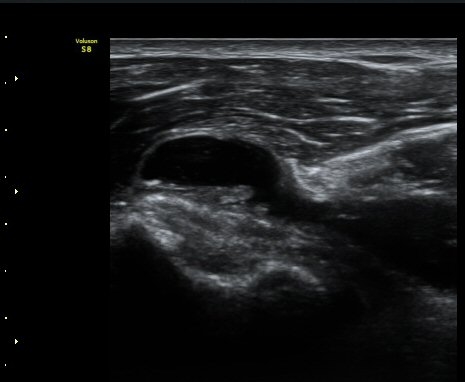

ÀÌµÎ¹Ú±Ù°Ç È¾´Ü¸é°Ë»ç¿¡¼­ °ÇÁÖÀ§¿¡ ¼Ò·®ÀÇ ¼ö¾×Àú·ù¿Í Á¡¾×³¶³» ¾×Àú·ù°¡ °üÂûµÈ´Ù(»çÁø 1, 2).